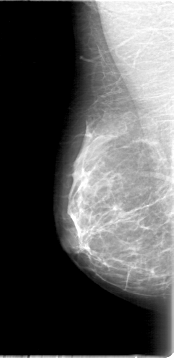

D_4000_1.RIGHT_MLO

RIGHT_CC LINES 5056 PIXELS_PER_LINE 2416 BITS_PER_PIXEL 12 RESOLUTION 43.5 NON_OVERLAY

RIGHT_MLO LINES 5386 PIXELS_PER_LINE 2596 BITS_PER_PIXEL 12 RESOLUTION 43.5 NON_OVERLAY